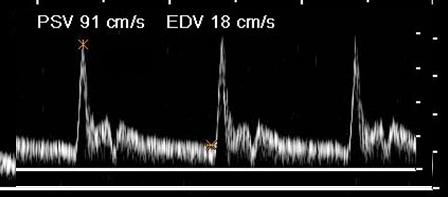

Where is the waveform?

ECA